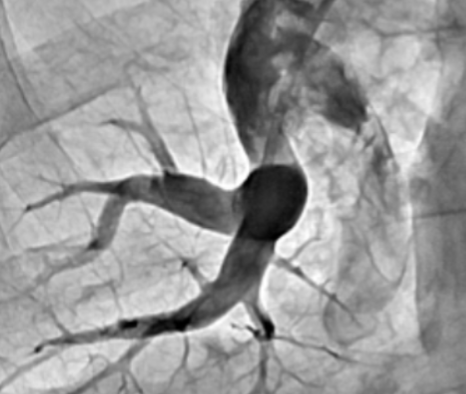

Nauja intervencinė kardiologijos procedūra – balioninė plaučių angioplastika (BPA) / www.santa.lt nuotr.

Santaros klinikų medikai pasakoja, jog procedūros metu per šlaunies veną (kirkšnyje) pasiekiamos susiaurėjusios plaučių arterijos. Įvedamas apie 1 metro ilgio ir apie 2 mm diametro kateteris. Per kateterį įvedama labai plona vielutė, su kuria į pažeistą kraujagyslę įvedamas balionas. Išplėtus balioną, susiaurėjusi vieta prasiplečia, pagerinama kraujotaka. Siekiant sumažinti komplikacijų (pvz., plaučių kraujagyslių sužalojimo, galinčio sukelti mirtį) riziką, procedūros atliekamos etapais. Tam pačiam pacientui planuojama nuo 4 iki 10 procedūrų maždaug kas 4 savaites. Kartojant procedūras, plečiamos tos pačios kraujagyslės kaskart vis didesnio diametro balionais iki optimalaus kraujagyslės dydžio. Etapais didinant baliono diametrą, išvengiama labai sunkių komplikacijų: kraujagyslės plyšimo ir kraujavimo į plaučius. Norint sustiprinti šios procedūros gydomąjį poveikį, svarbu pagerinti kraujotaką didesniame kiekyje pažeistų kraujagyslių, todėl procedūrą tenka kartoti keletą kartų.